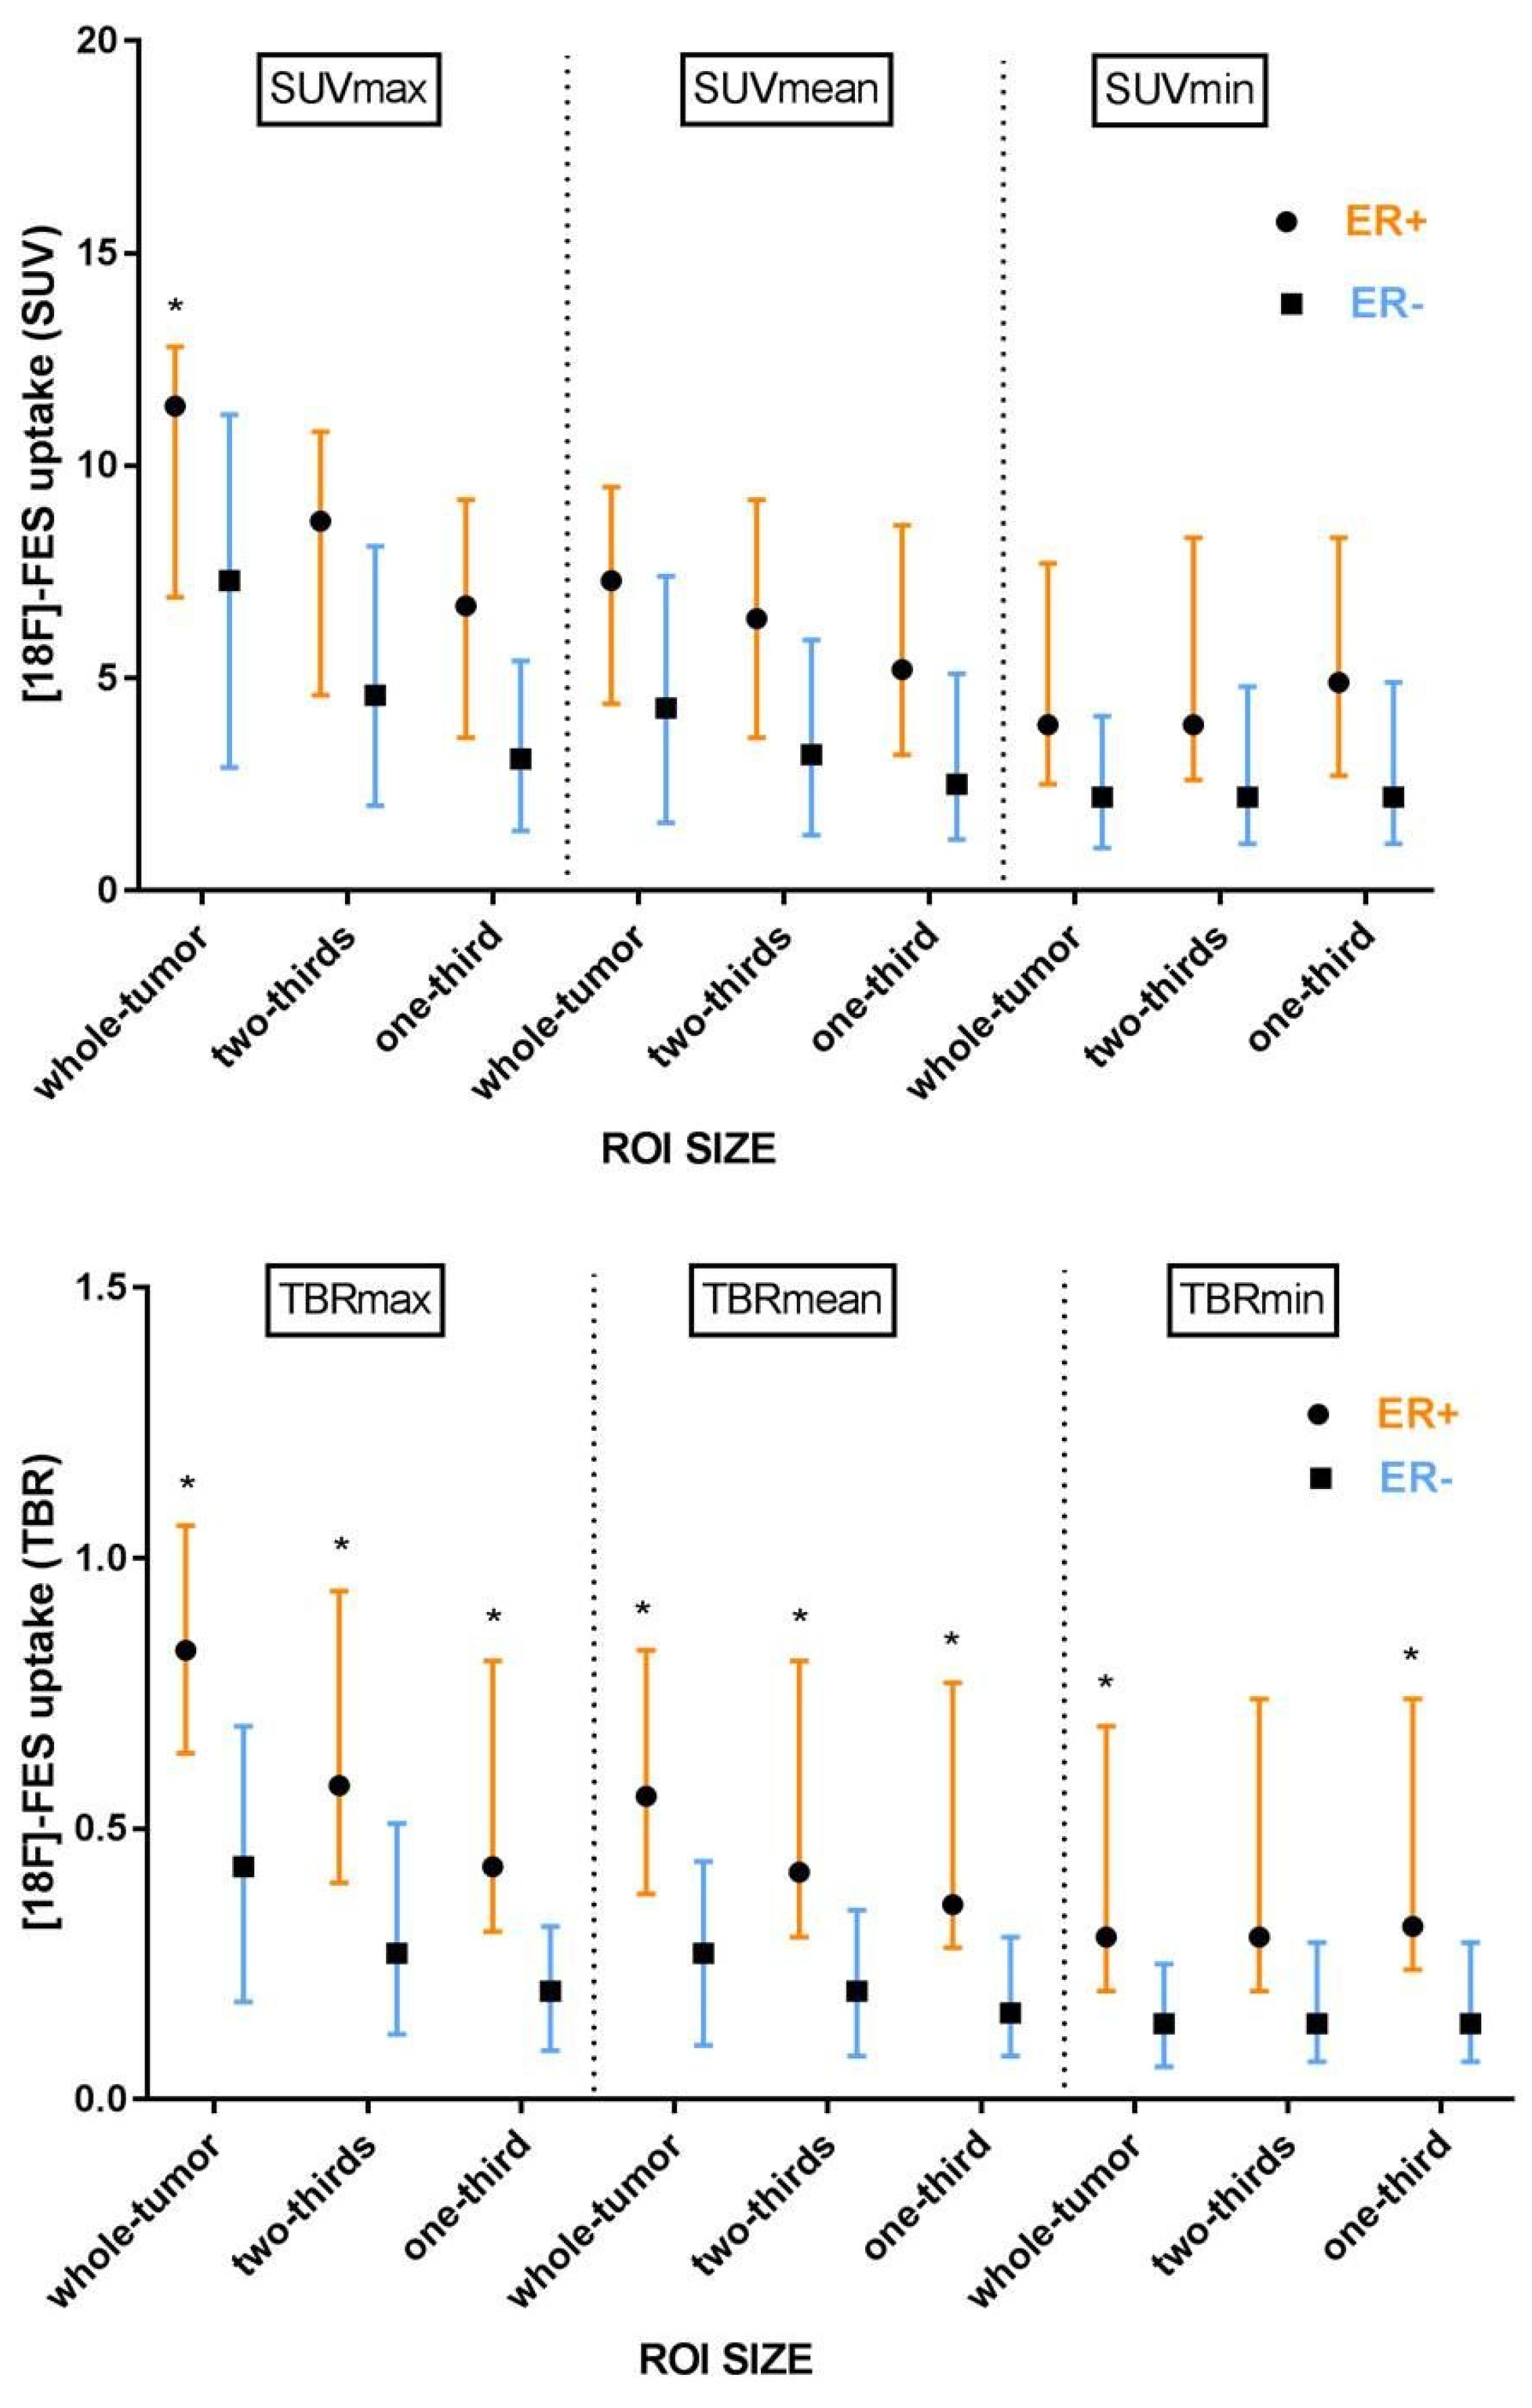

3.4. The Effect of ROI Size

3.5. Background Correction